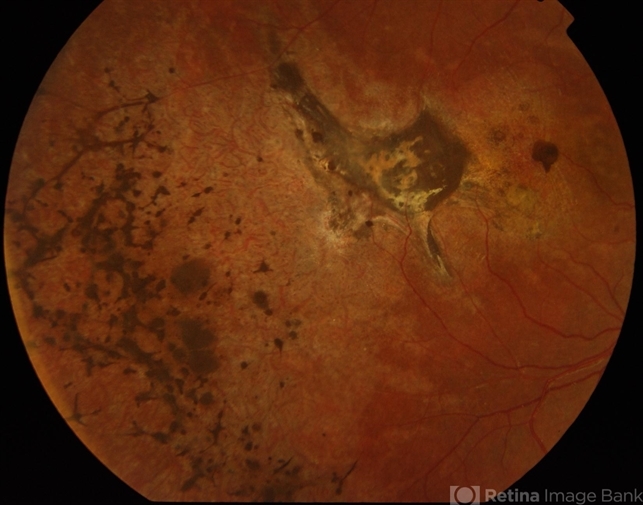

- macular scar

- Male patient, 15-years-old. Vision of the right eye is counting fingers and left eye is normal. It seems to be a case of macular scar in right eye.